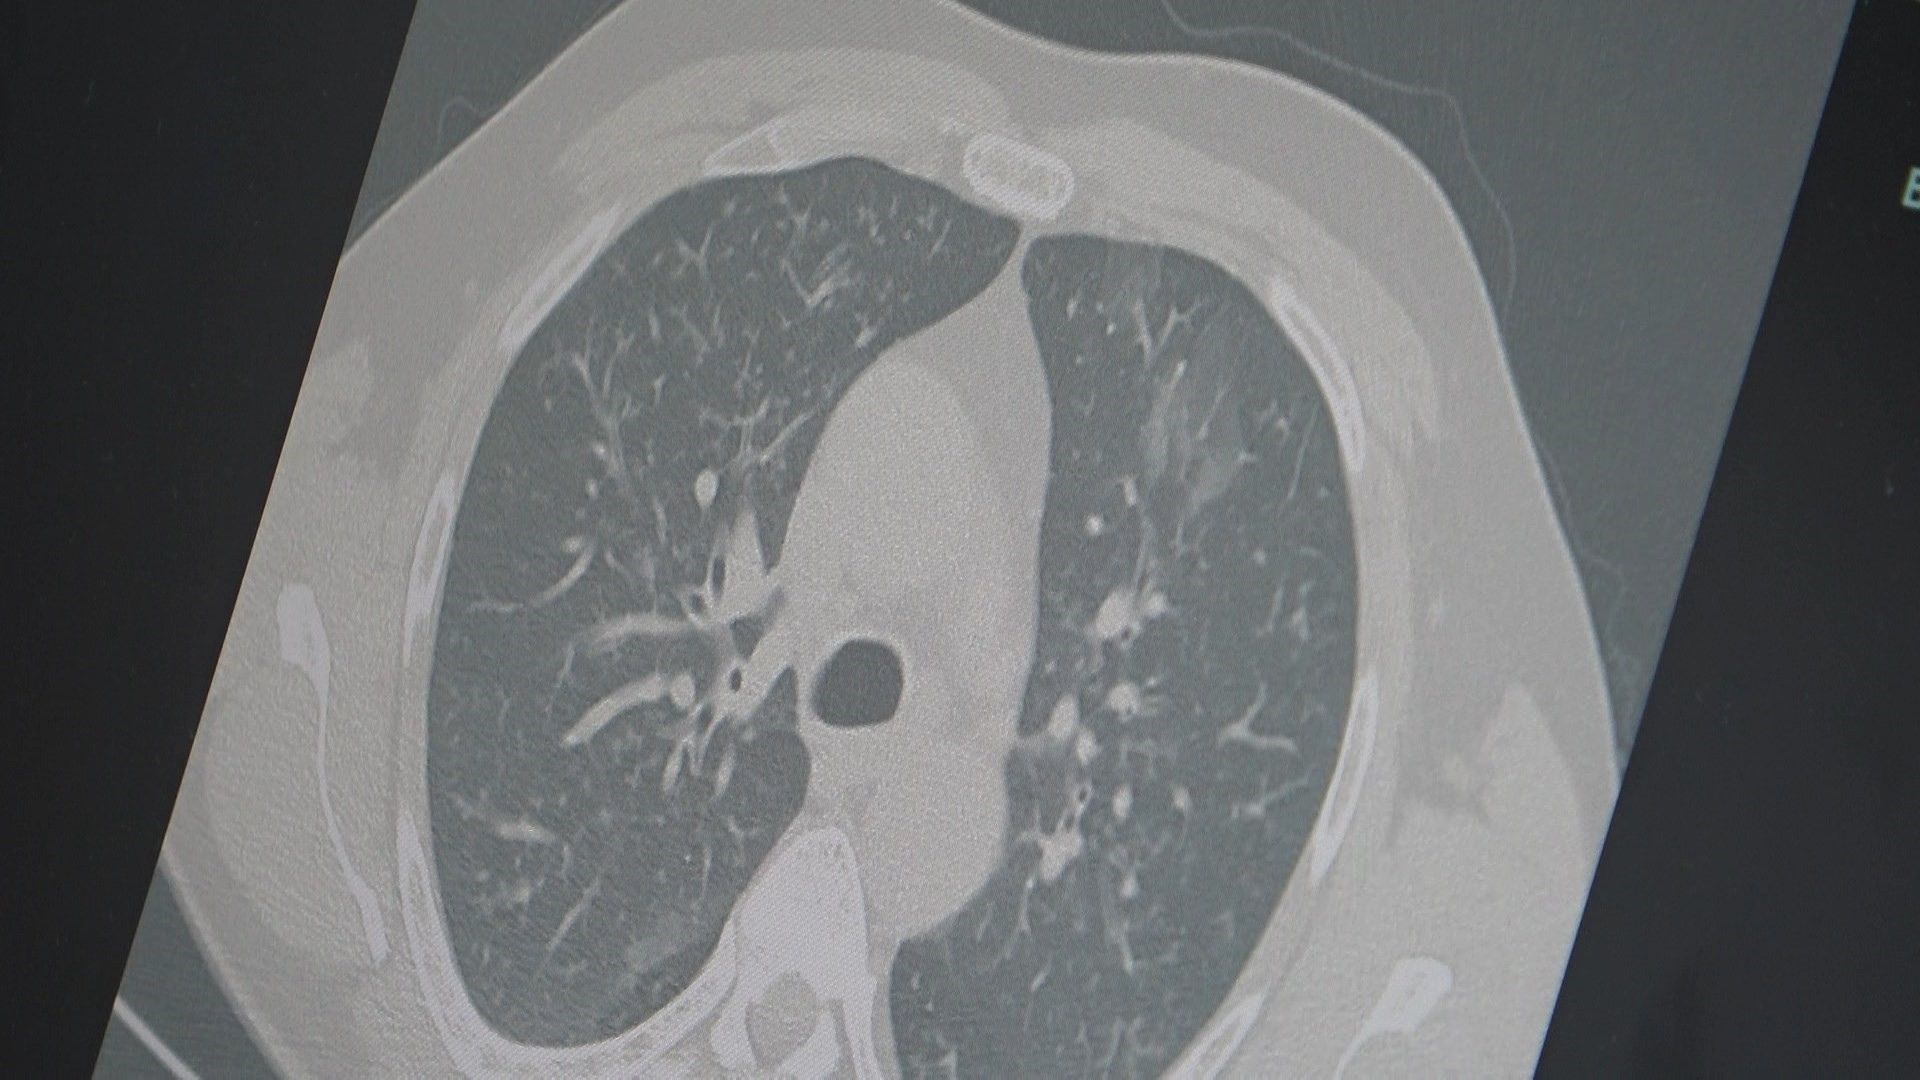

Grip ve kovid sonrası birçok hastada enfeksiyonun akciğerlere indiğini belirten Özkaya; “Hastaneye yatışlarda artış var, zatürre vakalarını daha sık görüyoruz” diye konuştu.

Özkaya; “Grip benzeri şikâyetlerde mutlaka dinlenin. Uzayan öksürük ve nefes darlığında akciğer filmi çekilmeli, tedavi ihmal edilmemeli” diyerek vatandaşları uyardı.